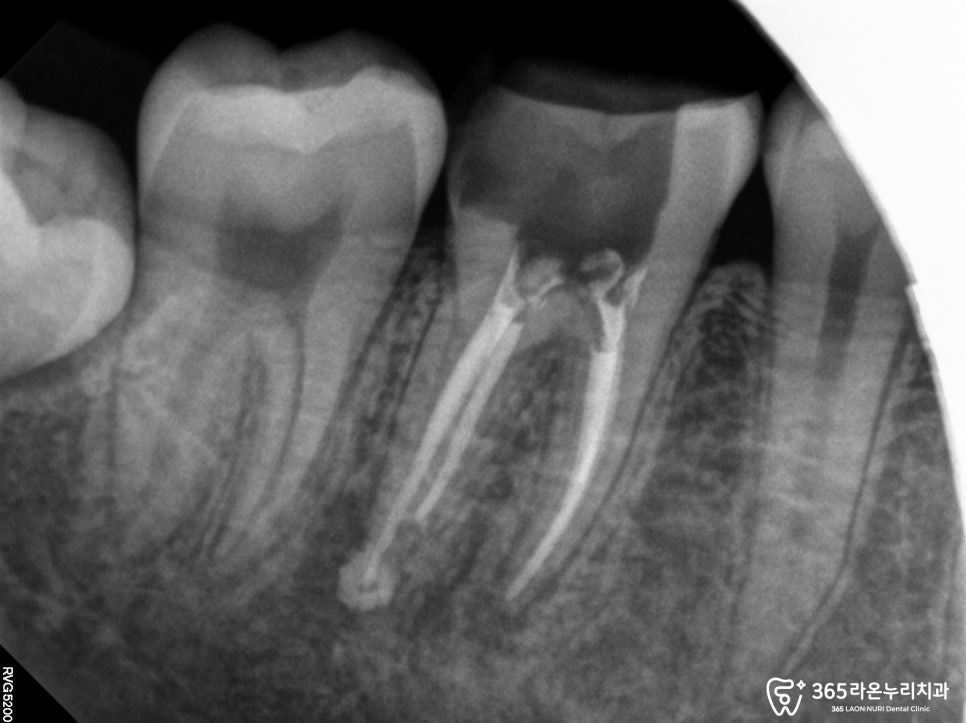

오산대역 치과 에서 사진에서 보면 뿌리 끝까지

잘 밀봉되어있는 것을 확인 할 수 있습니다.

치아의 손상 정도나 치아배열, 교합력등

다각도로 고려했을 때 오버레이(Overlay)가

가장 적합하다고 진단 내렸습니다.